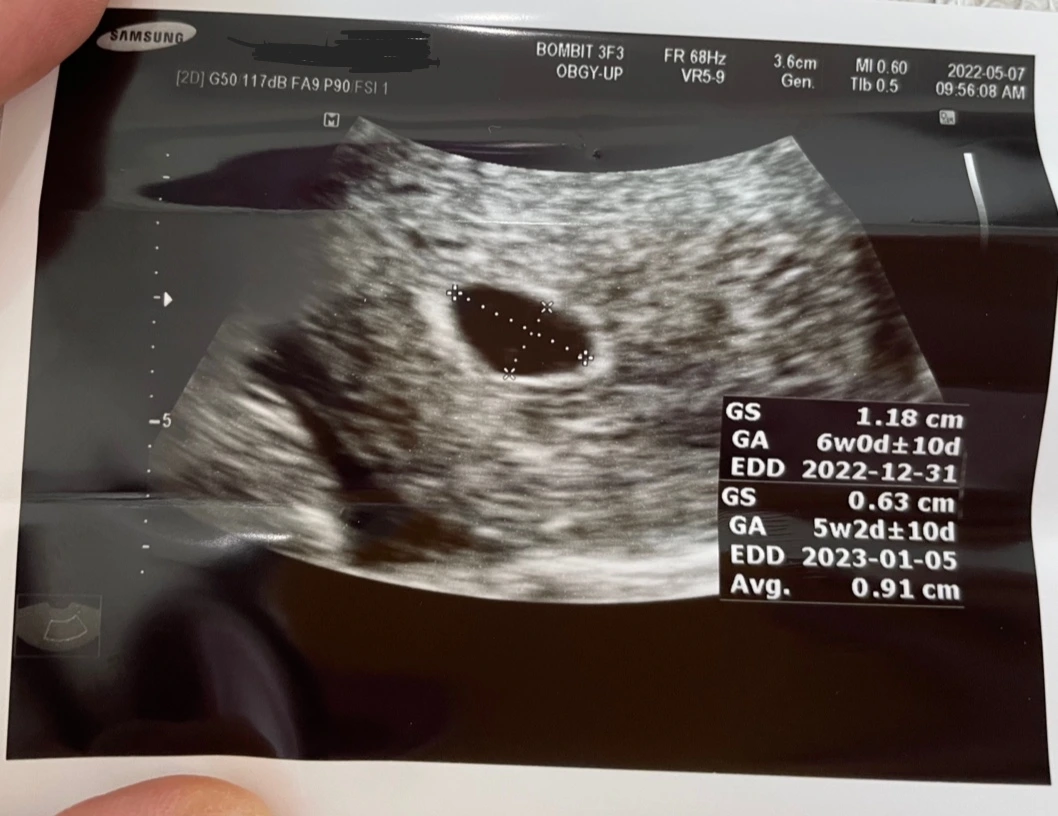

아기집과 난황

"오늘은 아기집이 보이네요."

질초음파로 내 자궁 속을 확인하자마자 내 눈에도 아기집이 보였다. 초점을 잘 맞추니 난황까지 보였다. 아기집의 크기를 재어 확인한 주수는 5주 2일.

주치의 선생님은 축하한다는 말과 함께 4장의 초음파 사진을 보여주며 설명해주셨다.

아직 아기는 안 보이는 시기로, 2주 뒤에 다시 내원하면 아기를 초음파로 확인할 수 있고, 심장소리를 들을 수 있다고 한다.

아기가 초음파로 보일 때, 아기 크기를 재어 정확한 주수를 다시 정할 예정이며 이에 따라 분만예정일이 변경될 수도 있다.

평균 0.91cm 크기의 아기집. 이 크기의 아기집은 통계적으로 5주 2일인가보다.